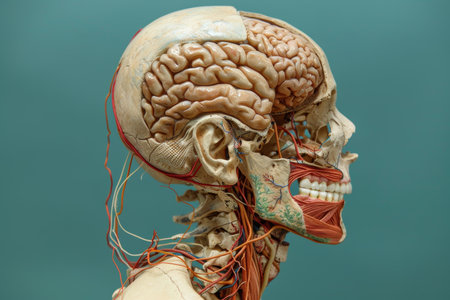

a human model with bones and muscles in a laboratory

Vibrant illustration of human anatomy showcasing the brain and neck. Ideal for medical, educational, and health-related projects to highlight inner workings.

a human model with bones and muscles in a laboratory

Detailed human skeleton face anatomy with brain, teeth, jaw, and nerves in head and skull structure